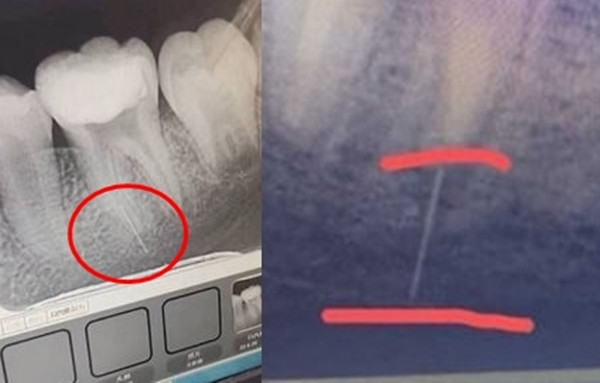

Chụp X-quang thấy kim bị gãy nằm ghim sâu vào nướu răng, thoạt nhìn đã thấy đau đớn. Lo lắng, cô Đường đã đưa con gái đi khám 2 lần nhưng vẫn không lấy được phần kim bị gãy ra, vì con gái còn quá nhỏ nên cô cũng không dám cho phẫu thuật.

Cô Đường tiết lộ thêm, hiện tại, mảnh kim gãy này chưa ảnh hưởng nhiều đến con gái cô nhưng nó lại nằm ở vị trí cực gần dây thần kinh trong nướu, điều này khiến cô rất lo lắng, mong bệnh viện nhanh chóng xử lý sự cố y tế này và đền bù chi phí điều trị cho gia đình. Tuy nhiên, phía nha sĩ hay bệnh viện vẫn chưa trả lời.